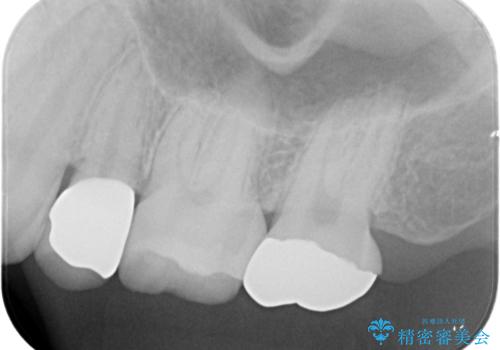

白くて適合の良い被せ物が入りました。

セラミックは劣化することがなく虫歯の再発のリスクが低くなります。